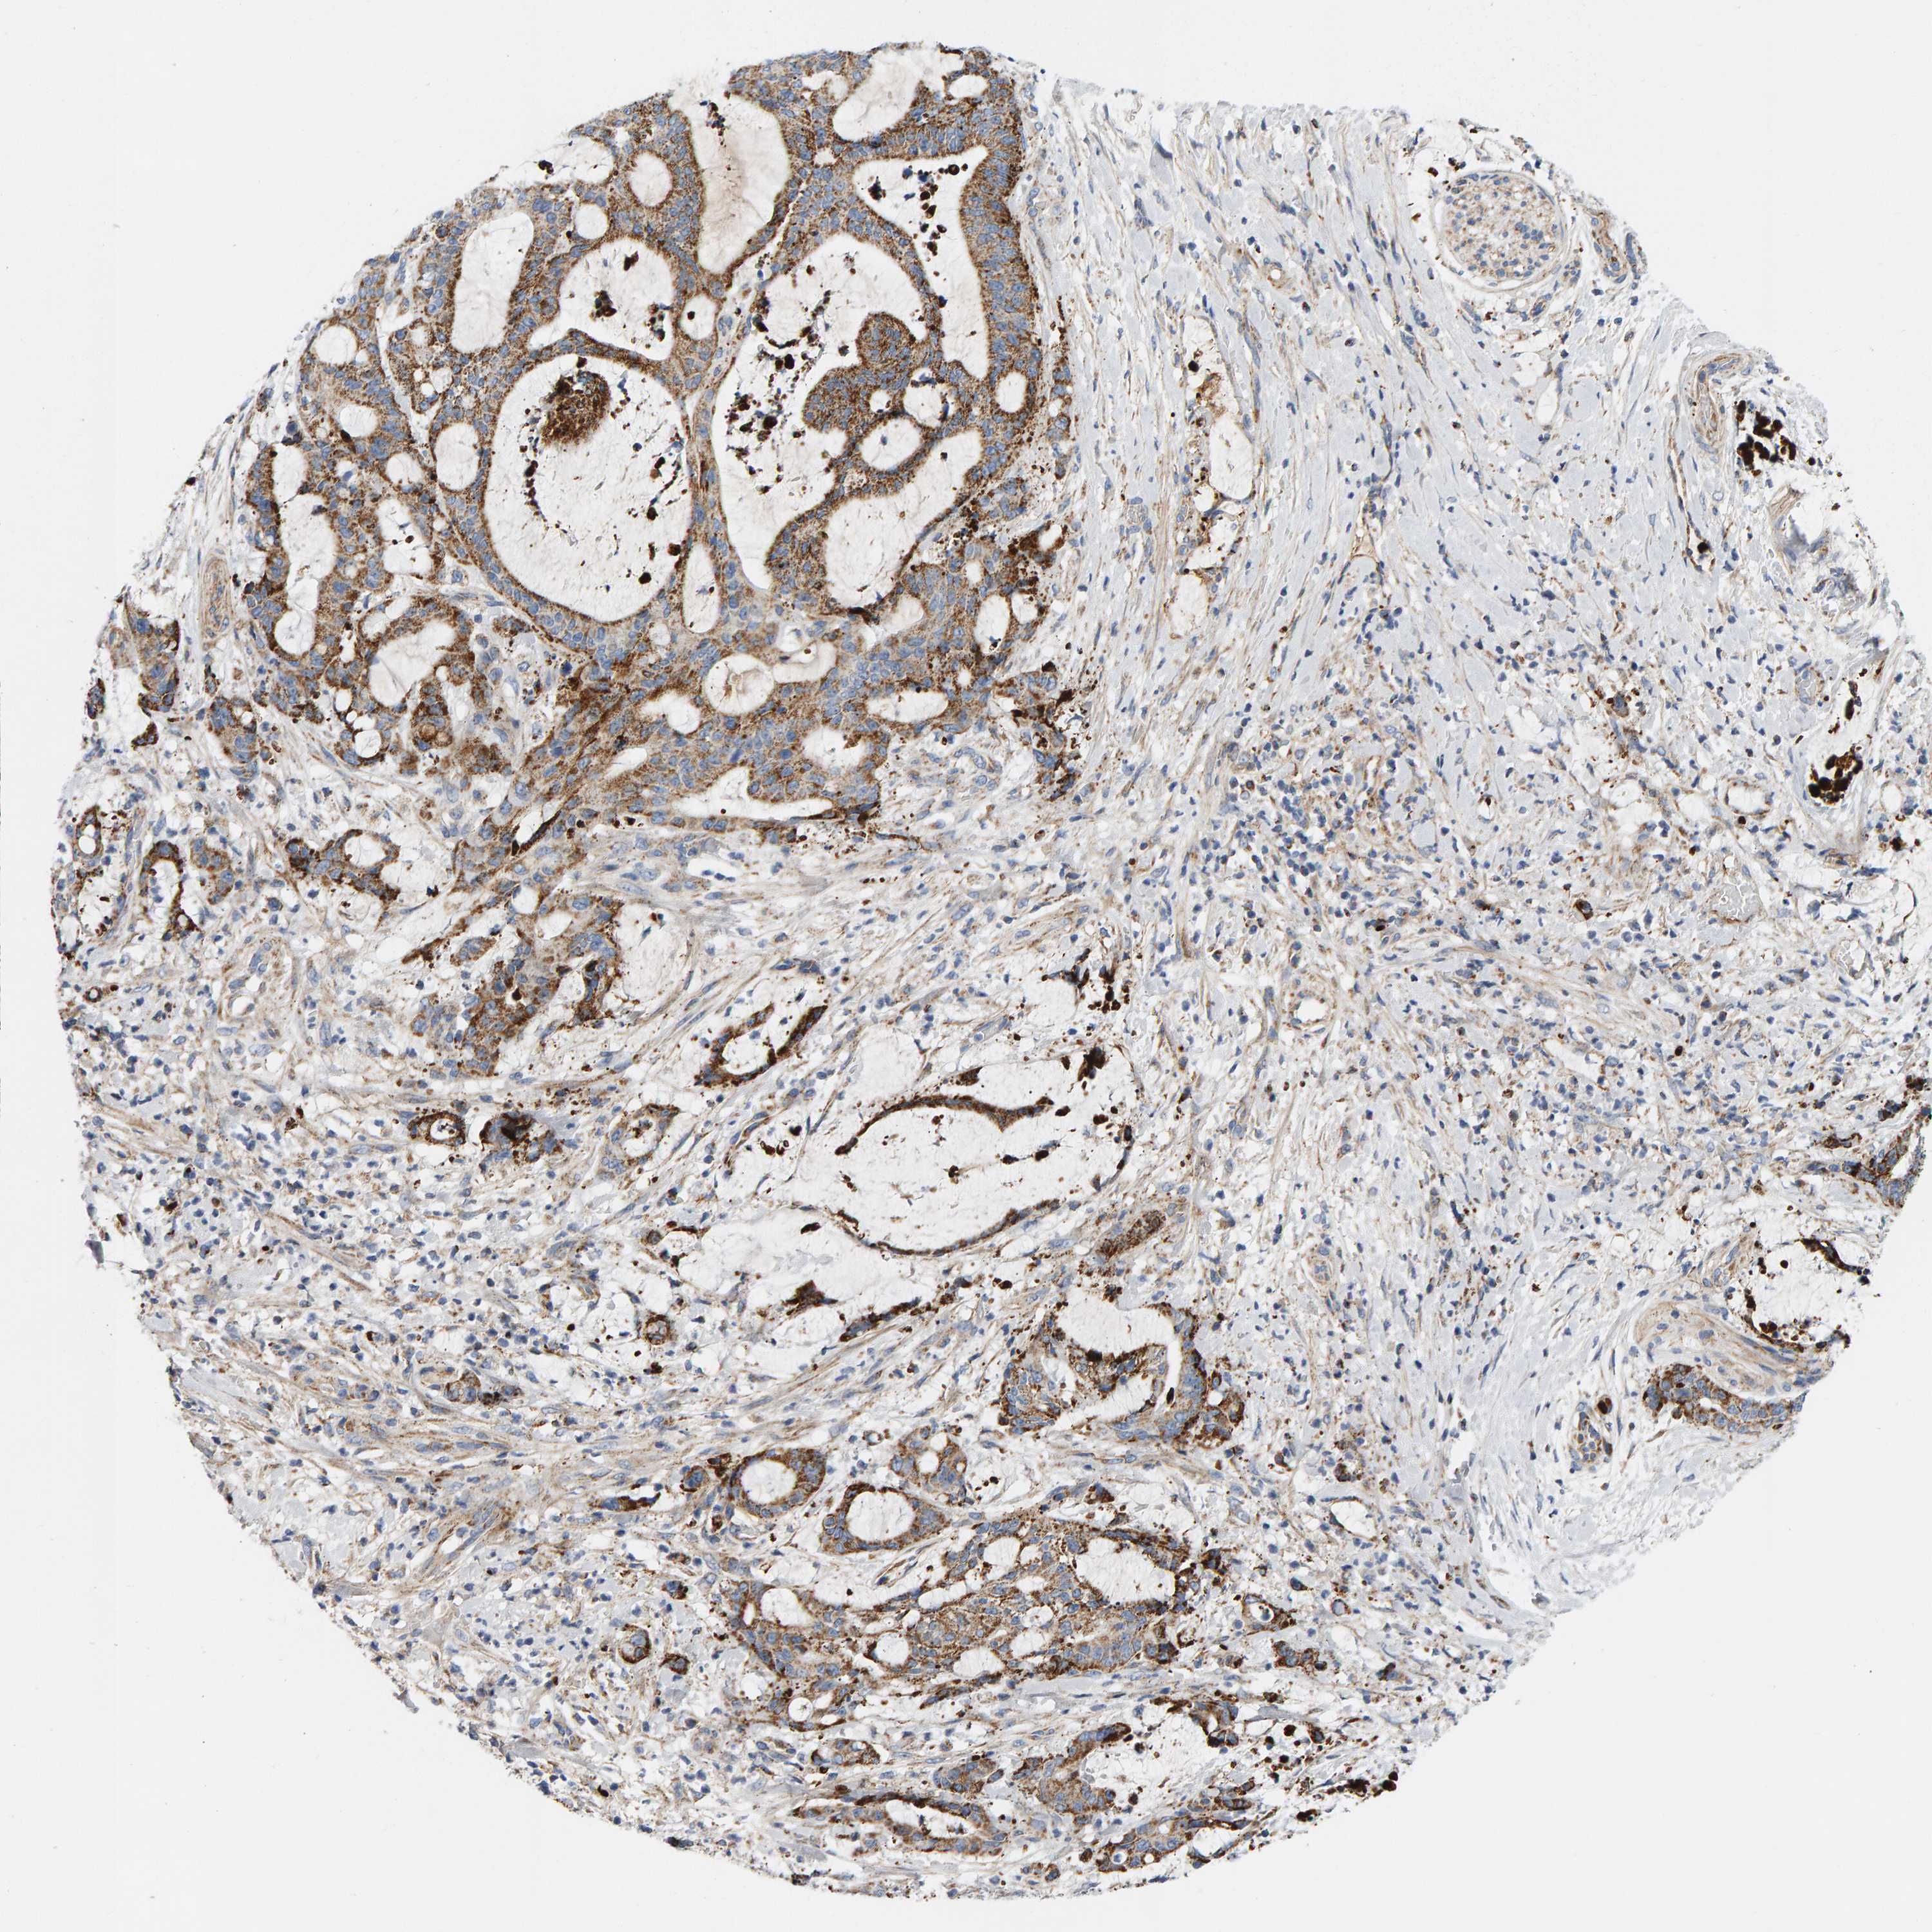

LIVER CANCER - Protein expressioni

A mouse-over function shows sample information and annotation data. Click on an image to view it in a full screen mode. Samples can be filtered based on level of antibody staining by selecting one or several of the following categories: high, medium, low and not detected. The assay and annotation is described here.

Note that samples used for immunohistochemistry by the Human Protein Atlas do not correspond to samples in the TCGA dataset.

Antibody stainingi

Antibody staining in the annotated cell types in the current human tissue is reported as not detected, low, medium, or high, based on conventional immunohistochemistry profiling in selected tissues. This score is based on the combination of the staining intensity and fraction of stained cells.

Each image is clickable and will lead to virtual microscopy that enables deeper exploration of all samples and also displays staining intensity scores, fraction scores and subcellular localization as well as patient and tissue information for each sample.

Antibody HPA023262

Staining

High

Medium

Low

Not detected

Intensity

Strong

Moderate

Weak

Negative

Quantity

>75%

75%-25%

<25%

None

Location

Nuclear

Cytoplasmic/membranous

Cytoplasmic/membranous,nuclear

Cholangiocarcinoma

Carcinoma, Hepatocellular, NOS